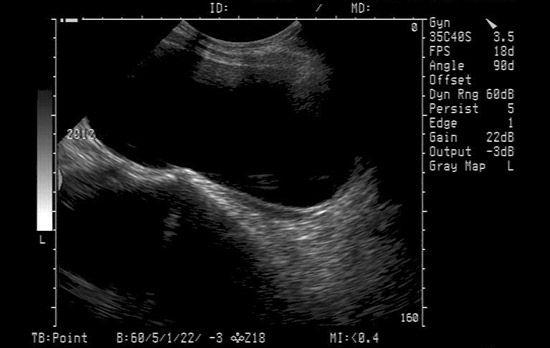

阴道四维彩超下的始基子宫影像

始基子宫又叫痕迹子宫,是临床上比较少见的一类子宫发育畸形疾病,造成始基子宫的原因主要是由于女性生殖系统先天发育不良所致,多见于副中肾管发育异常。主要的表现症状为子宫极小,仅1-3厘米,多无宫腔,合并无阴道,无月经。

临床上针对始基子宫的诊断主要是依靠病史、临床表现,以及妇科B超、彩超、染色体分析和内分泌检查等进行的,一般来说实体性始基子宫往往不予处理,但如果出现周期性腹痛或宫腔积血,就需要考虑手术切除。